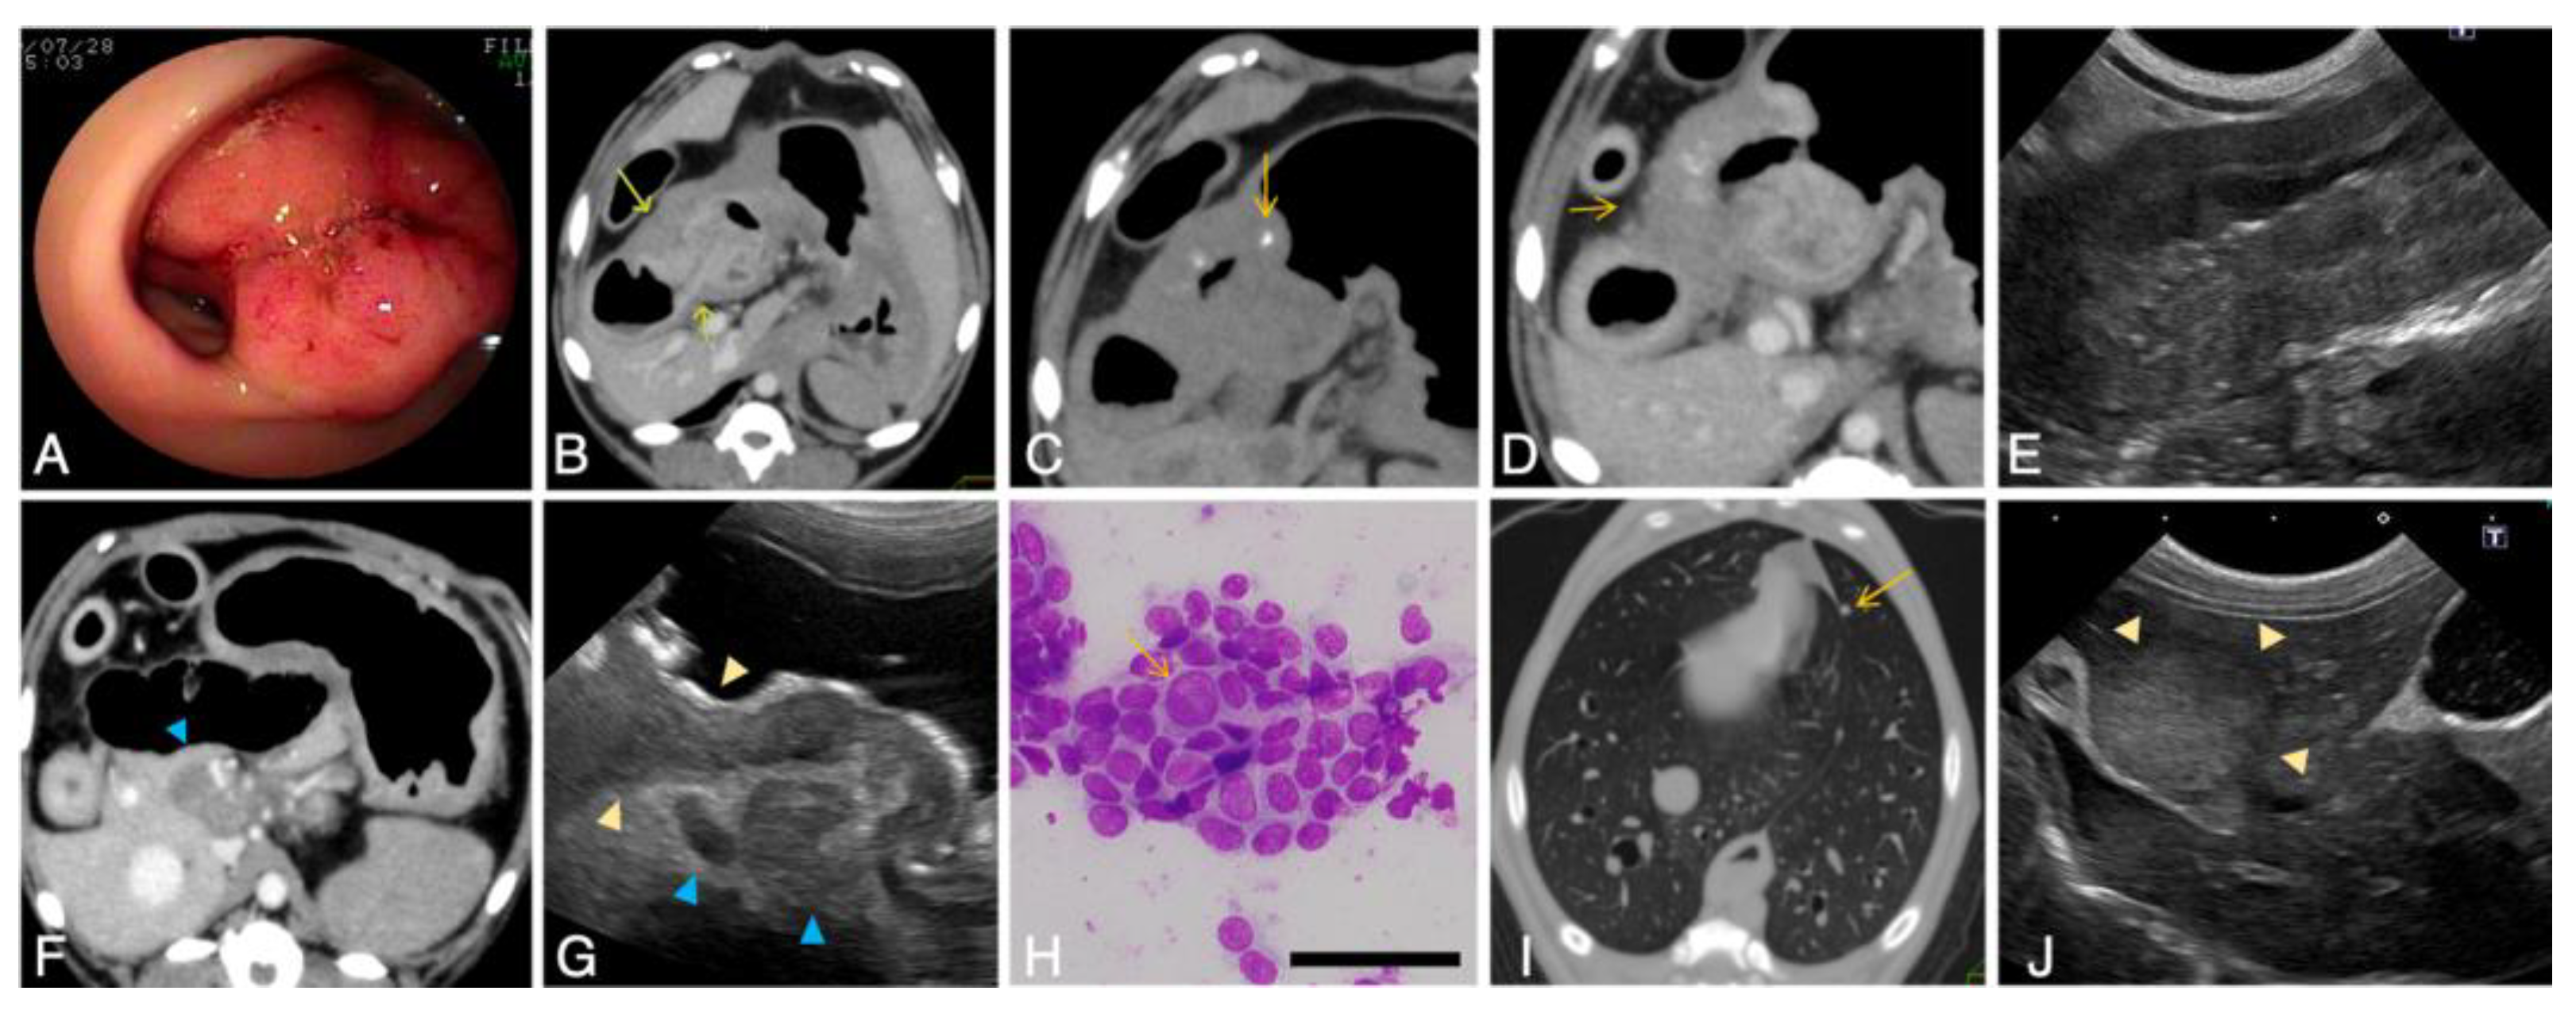

3.1.5. Diagnostic Imaging

Radiography

Ultrasonography

CT Scan

Endoscopy

Diagnostic Imaging of Invasive and Metastatic Tumors